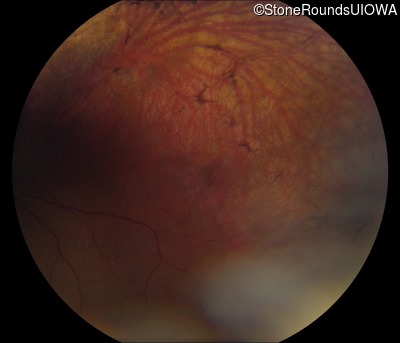

Fundus Photography - Left - 20/50 -3

Exemplar